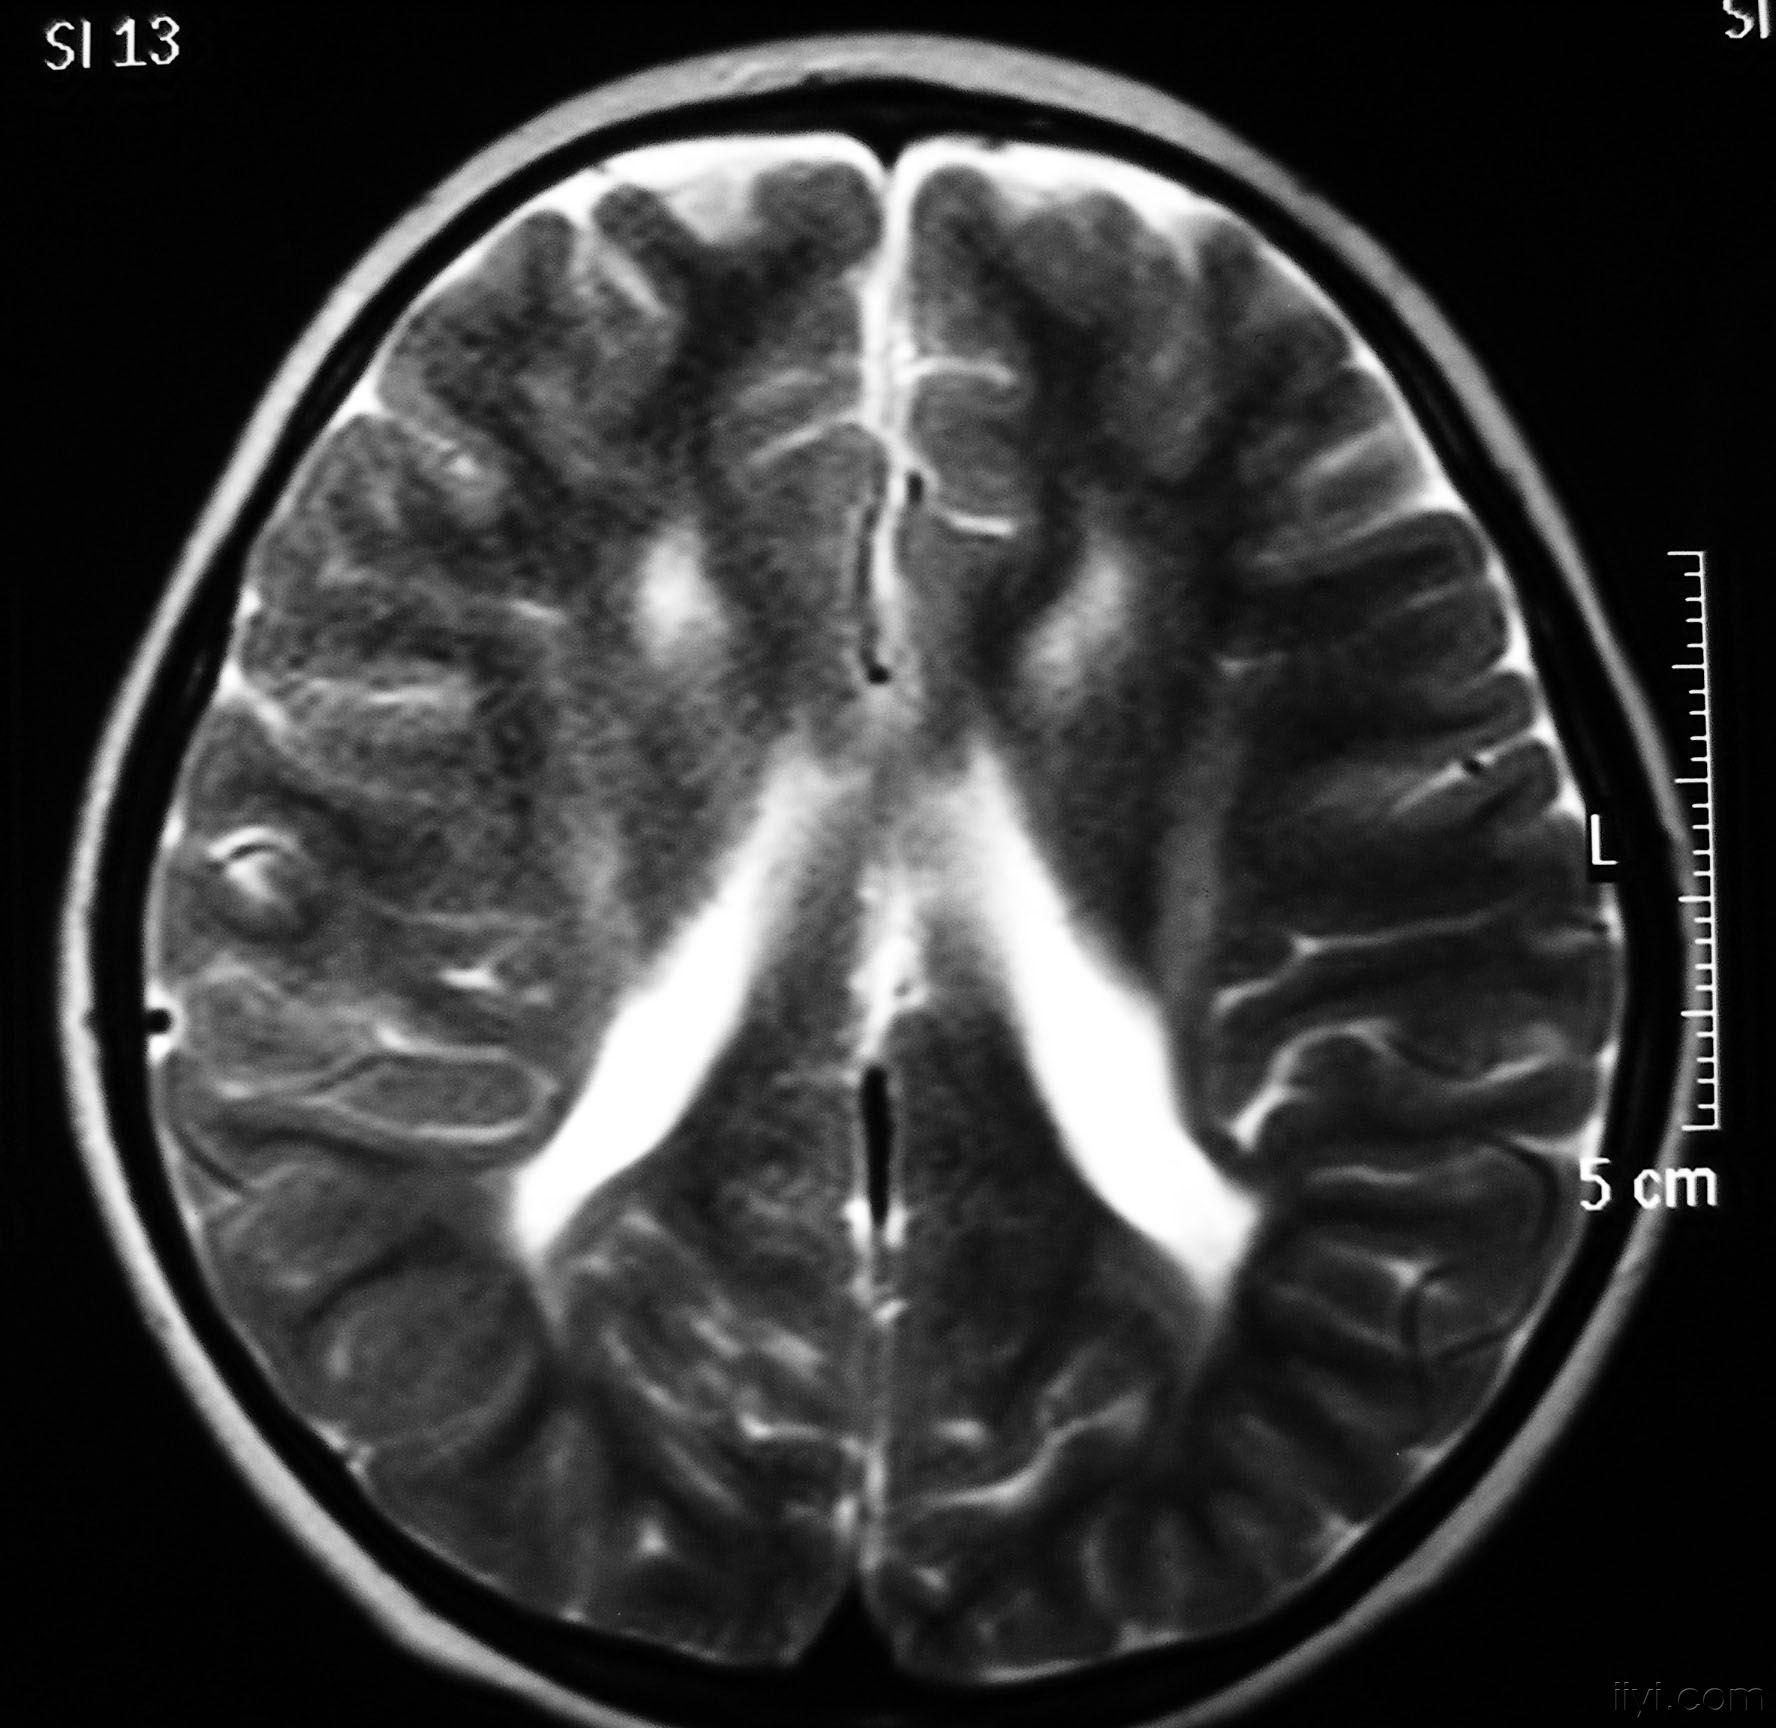

pvL

主要与脑缺血缺氧有关,多见于早产儿,是造成脑瘫的主要原因

影像学发生于侧脑室周围,侧脑室扩大,脑白质减少。扩大的侧脑室外缘常不规则为其特点,多为双侧脑室同时扩大。脑白质减少,脑皮层与脑室侧缘相近。MRI T1呈低信号,T2呈高信号。